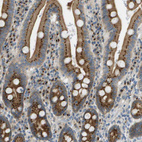

Immunohistochemical staining of human placenta shows strong granular cytoplasmic positivity in trophoblastic cells.